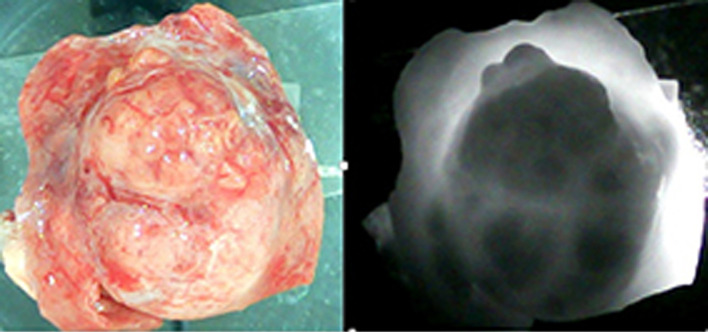

Methods: The infrared (IR) imaging approach uses the differences in optical density between tumor and healthy tissue to create the sharp contrast in the IR images. The cancerous kidneys were examined after a radical nephrectomy. Following the removal of the cancerous tissue and some of the surrounding healthy tissue, the samples were examined using the IR method. For the IR analysis, we created specific software. Following that, tissue samples taken from both healthy and malignant areas were subjected to a histomorphological analysis.

Results: Experiments showed that malignant tissue appeared as areas of high blackness in the IR picture, while healthy tissue appeared as areas of high illumination. Our software highlighted the areas of the IR image that were associated with the healthy and malignant portions, computed their average brightness, and calculated the ratio of the average illumination (RAI) of the malignant area to that of the healthy area. RAI is an interval of numbers obtained as a result of dividing the average brightness of all dark areas in all examined samples by all light areas of all examined samples. The 95% probability interval for RAIs taking place, which ranged from 0.25 to 0.41, was calculated. The location of the malignancy was then identified by a histomorphological examination. The compliance between histomorphological results and the outcomes of IR examination was confirmed in all cases.